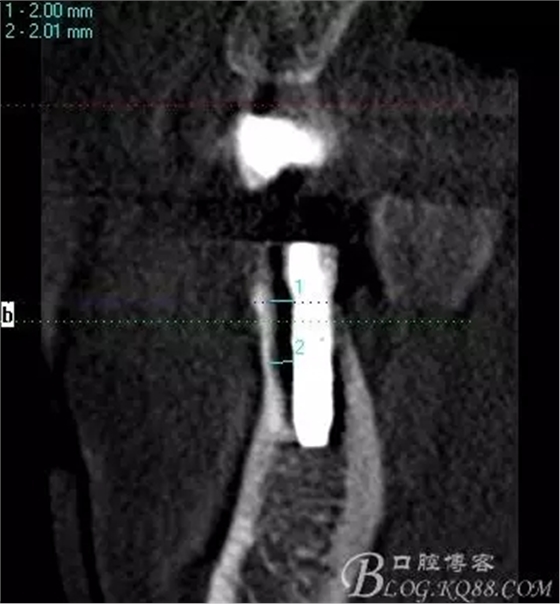

簡(jiǎn)單備洞以后植入種植體 植體和頰側(cè)空間距離大于2毫米 注意沒有植骨

術(shù)后片 能顯示間隙沒有植骨是空的